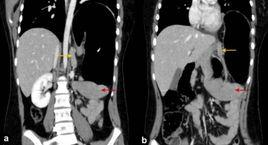

腎下垂是指直立時,雙側腎臟下降大於4cm。多數發生於20~40歲女性及瘦長體型者。右側多於左側。主要表現為腰痛、勞動及行走時加劇,平臥後消失。腎蒂扭轉時,發生Dietl危象,即腎絞痛、噁心、嘔吐、脈快甚至高血壓、血尿等。腎下垂有時導致腹腔神經紊亂,表現為消化不良、腹脹、噯氣、噁心、嘔吐等。應與腹部包塊鑑別。X線及超聲有助診斷。一般不須治療。嚴重者行腎懸吊固定術。

腎過度向下移動而產生的臨床症狀。由於腹膜後脂肪組織過少,腹壁鬆弛或腎窩過淺,均可使腎在站立時向下移動,其移動超過一個椎體厚度時為腎下垂。移動度過大且能左右移動者為遊走腎。常伴有胃或全內臟下垂。多見於體高,消瘦和多產婦女。以右側為多見。多無自覺症狀,或有腰痛或上腹部包塊。極少數患者出現腎絞痛。立位和臥位尿路造影根據腎移位程度可以確診。有症狀者可通過腹肌鍛鍊,提高體重或用腹帶等非手術治療。嚴重者須行腎固定術。

由於腎筋膜前後兩層在下方癒合不牢固,故不能很好地固定腎,所以腎臟會向下異常遊走。當直立時,其下降可能超過3cm。當腎臟向下遊走時,腎上腺仍停留在原位置上,這是因為腎上腺位於獨立的筋膜間隔內並且與膈緊密粘著。腎下垂(腎向下遊走)與異位腎(腎先天性錯位)是有區別的:前者輸尿管長度正常,但由於腎與膀胱的距離短,故鬆散地盤繞或扭轉。輸尿管扭轉不會引起嚴重後果,但牽拉腎血管常會引起腎區的間歇性疼痛,平臥位疼痛可緩解。腎臟下方在腰區缺乏支撐是腎移植術將腎置於大骨盆腔髂窩內的原因之一(另一原因是該處有可被利用的大血管而且距膀胱近便於與膀胱相接)。